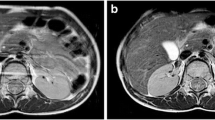

Liver T2 and T2* quantitative methods are routinely used clinically for body liver iron assessments (Fig. 10) [21,22,23,24]. Measured mean cardiac T2*, liver T2 and liver T2* can be converted to cardiac iron or liver iron concentrations (LIC) by published formulae [23, 25, 26].

T2 and T2* applications in liver imaging. a Axial T2-W fat-suppressed MR image in a 16-year-old boy with sickle cell disease who is transfusion-dependent. b Liver iron concentration (LIC) measured with T2*-based images is 8.4 mg/g. The same boy was scanned approximately 14 months after chelation therapy, and his estimated LIC was 3.6 mg/g. This is also reflected in the signal intensity of the individual increasing echoes. TE echo time. c Top row shows axial images of the liver, which can be seen getting progressively darker with increasing echo images when LIC measured was 8.4 mg/g. Bottom row shows axial images of the same boy with LIC measured at 3.6 mg/g approximately 14 months later after chelation therapy